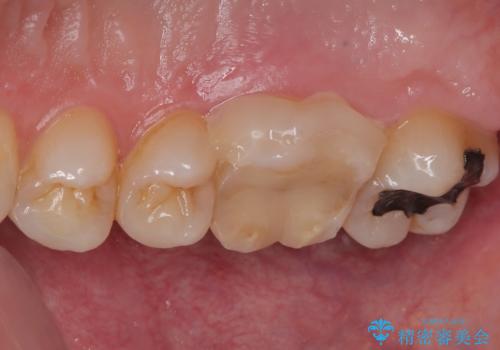

- 歯が割れたことを主訴に来院された患者様です。割れた原因としては噛み合う歯が強化セラミックスのみでできたフルジルコニアクラウンであったことと、大きな詰め物が入っていて自分自身の歯の範囲が少なかったことが考えられます。応急で来院されたときには暫間的に強力な接着剤で固定しました。

CT を撮影して確認したところ、歯肉より4ミリ程度深い場所で破折していました。患者様と相談して、外科的な介入はせずに被せもののみでの治療を行うこととしました。

拡大鏡視野下で詰め物と虫歯の除去を行い、詰め物の範囲が大きかったためオールセラミッククラウンに適した形に整えました。